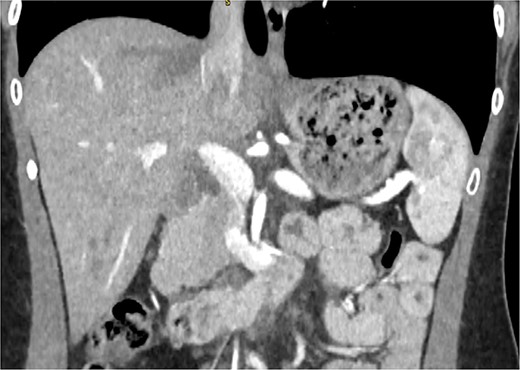

A 29-year-old female, with a past medical history of asthma and anxiety, presented to A&E Department at Mater Dei Hospital in view of a 2-day history of worsening right-sided colicky flank pain that radiated down to the right iliac fossa. Pain relief, including paracetamol and NSAIDS, alleviated her symptoms temporarily; however, pain recurred after a few hours. At A&E, patient’s parameters were noted to be stable throughout the review. On examination, the patient’s abdomen was noted to be soft with tenderness over the right flank. No guarding was noted, and renal punch was negative bilaterally. Blood investigations were all within normal limits, and urinalysis was normal. In view of the examination findings, a computed tomography (CT) of the kidney, ureters, and bladder was ordered, which noted an enlarged pancreatic head measuring 3 cm in diameter with noted upstream atrophic changes in the body and tail with fat stranding; prominent mesenteric lymph nodes were also noted. Based on the previous CT findings, a contrast CT of the pancreas was ordered, which revealed that the body and tail of the pancreas were absent; however, the pancreatic head was noted to be enlarged. This can be seen in Figs 1 and 2. Prominent lymph nodes with ground glass changes in the mesenteric fat were noted. CT pancreas therefore confirmed the diagnosis of dorsal agenesis of the pancreas. The patient was discharged home on pain relief and an outpatient’s appointment with the hepatobiliary team. Upon review at outpatients, the patient was well. She noted that she had been complaining of intermittent right loin pain over the past 3 years. Over the 2 months from review at A&E, the patient was well and denied further abdominal pain. In view of this, the patient was reassured and discharged. She was advised to seek medical advice should symptoms recur.

CT pancreas demonstrating absent body and tail of pancreas in coronal view.